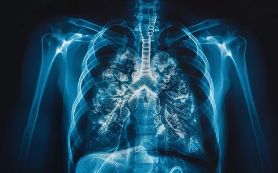

넘어지거나 부딪히는 등 강한 충격을 받으면 늑골(갈비뼈) 골절이 발생할 수 있습니다. 늑골 골절은 숨을 쉴 때마다 극심한 통증을 유발하며, 심한 경우 폐나 다른 장기 손상으로 이어질 수 있는 위험한 질환입니다.

늑골 골절은 단순히 뼈가 부러지는 것에 그치지 않고, 다양한 후유증을 남길 수 있습니다.

2. 호흡 곤란: 숨 쉴 때마다 답답함

늑골 골절은 폐 기능 저하로 이어져 호흡 곤란을 유발할 수 있습니다. 특히 다발성 늑골 골절이나 흉곽 골절의 경우 흉벽의 안정성이 떨어져 호흡 운동이 제한되고, 폐렴, 무기폐 등 합병증 발생 위험이 높아집니다.